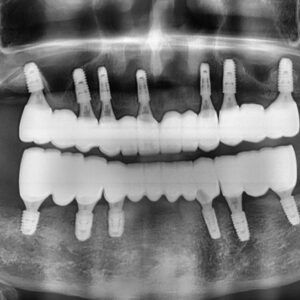

또한, 트리오스5 의 첨단 인공지능 기술을 통해

교합 위치, 교합 간섭, 교합 정도를 구체적으로 확인할 수 있어

더욱 정밀하고 정확한 보철 제작이 가능합니다.

충치치료, 보철치료 뿐 아니라,

임플란트 보철 치료에도

모두 사용 가능합니다.